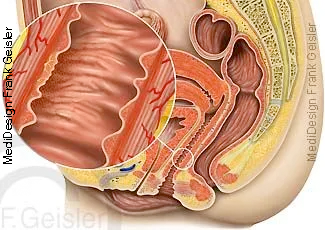

Längsschnitt durch die Beckenorgane und Geschlechtsorgane der Frau; Gräfenberg-Zone, G-Punkt, eine erogene Zone der Vagina

Bei der Gräfenberg-Zone, auch G-Zone sowie G-Punkt oder G-Spot, handelt es sich um eine erogene Zone in der Vagina. Bei manchen Frauen soll ihre Stimulation sehr schnell zu einem Orgasmus führen, andere empfinden diese jedoch als wenig oder nicht erregend. Die Zone liegt etwa 3 bis 5 cm vom Scheideneingang entfernt an der Vorderwand der Scheide, zur Bauchdecke hin, unmittelbar hinter dem Schambein. Sie ist etwa 2 cm im Durchmesser. Ein Merkmal des G-Punktes ist, dass sich das Gewebe an dieser Stelle rauh, gerippt oder fester anfühlt, während die übrige Scheidenwand glatt ist.